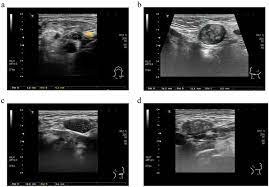

They may put a small, thin camera down your throat to look for problems, a procedure called a laryngoscopy. Also, would throat cancer cause a lump like this growing on the outside of the throat/neck? The most common symptom of thyroid cancer is a hard lump on the neck—but most patients experience no symptoms at all. Keep in mind, however, that an ultrasound alone cannot make the diagnosis of cancer. For example, throat cancer pictures below are three stages of cancer of the tonsils. Throat cancer is a malignancy of either the tonsils, pharynx, or larynx. Thyroid nodules are lumps that can appear in the thyroid gland in front of the throat. Each subtype of throat cancer has its own criteria for each stage.

The initial stage of throat cancer will start with vague and nonspecific symptoms and later it will start developing into unresolved lump or growth. A small transducer (probe) both transmits sound waves into the body and records the waves that echo back. Cervical cancer requires specialized care. If the fna shows cancer, the pathologist (the doctor examining the samples) can often tell what type of cancer it is. An ultrasound may show your doctor if a lump is filled with fluid or if it's solid. If the cancer cells look like they might have come from the larynx or hypopharynx, an endoscopic exam and biopsy of these areas will be needed. They may put a small, thin camera down your throat to look for problems, a procedure called a laryngoscopy. Within the first two days of the patient's arrival at our hospital.